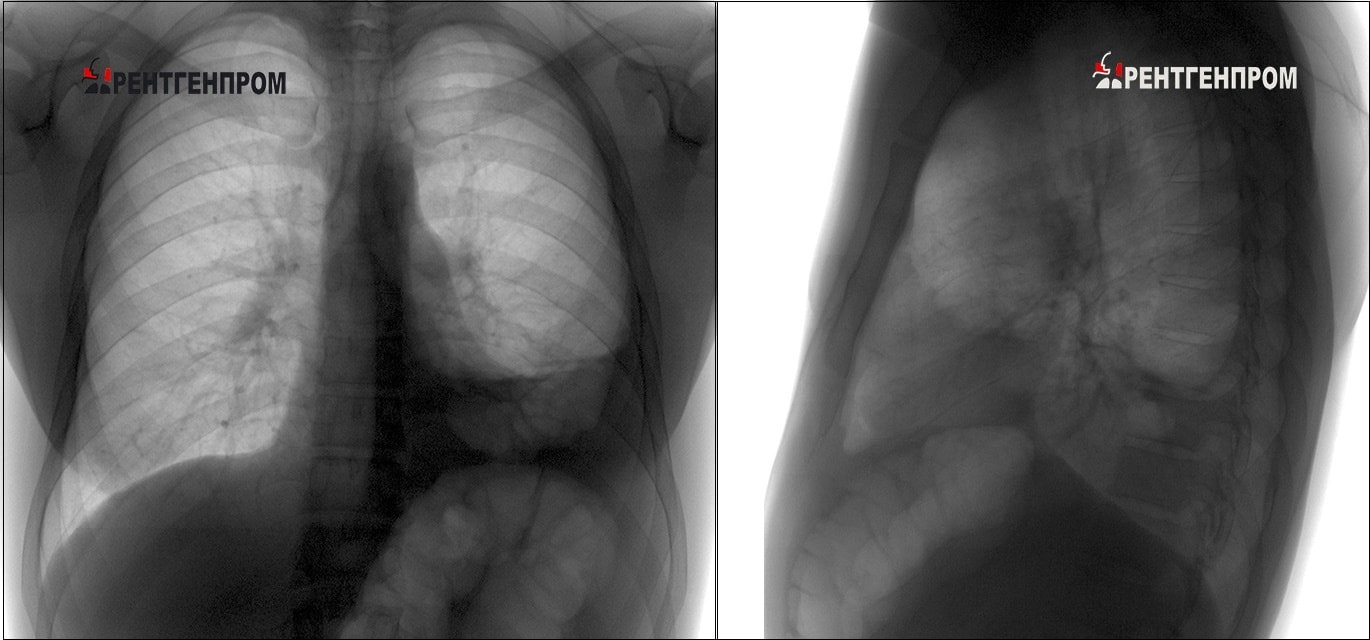

После проведения рентгенографии снимки должен изучить специалист, и на основе полученных данных и результатов других исследований сделать соответствующие выводы и поставить диагноз. В норме легкие и бронхи человека выглядят следующим образом:

- легочные доли имеют одинаковый, равномерный черный оттенок;

- в районе сердца наблюдается белый просвет;

- ребра и ключицы серые, с привычными очертаниями;

- купола диафрагмы белого цвета;

- позвоночный столб расположен в центре.

Конечный результат картинки получается неоднородным. При здоровых легких структура как раз отличается однородностью. Если присутствует пневмония, на рентгеновских снимках затемненные участки уплотнений указывают на очаги воспаления. Высветленные участки – ткани воздушные. Диагноз пневмонии по снимку ставится в том случае, когда имеются: